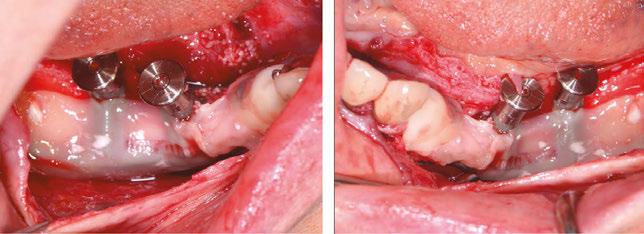

A 59-year-old male reported to the dental office with missing maxillary teeth due to poor oral hygiene. Treatment planning was done for All-on-4 implant placements followed by prosthesis. A complete medical history was obtained and was negative for any significant medical problems. The patient denied being allergic to any medication as well. The patient agreed to the implant placement and was advised to have an orthopantomogram (Figure 1).

On the day of the surgery, before commencing the procedure under strict asepsis, the patient was asked to rinse with 0.12% chlorhexidine gluconate mouthwash (Peridex™; 3M™). Local anesthesia with a vasoconstrictor was infiltrated buccally and palatally into the posterior and anterior maxilla on both the sides using S-blades (straight) (Zabby, India). The incision was made

on the crest of the ridge in the region of teeth Nos. 15-25. While creating the incision, bleeding was noticed in the region of tooth No. 15 which intensified during the flap reflection (Figure 2). Bleeding was pulsatile, indicating an arterial bleed. Initially attempts to control bleeding included a pressure pack and ice pack, and the bleeder was isolated and the vessel ligated (Figure 3). The bleeding could be controlled, and the procedure was completed by placing four Bioner implants (Bioner, Spain), size 4/10 mm. Sutures were placed, and patient was kept on basic medication for pain and infection control. Immediately after the surgery, the patient was advised to get a CBCT. As shown in Figure 4, a coronal view and Figure 4B (yellow arrows), the position of the artery can be seen.

Figure 1: Pre-op panoramic radiograph

Figure 2 (left): Alveolar antral artery (AAA). Figure 3 (center): The artery has been ligated with suture. Figures 4A and 4B (right): CBCT post-implant placement and position of the artery coronally (top). 4B. Showing the position of alveolar antral artery (AAA) in relation to implant placement as indicated by the yellow arrows (bottom)